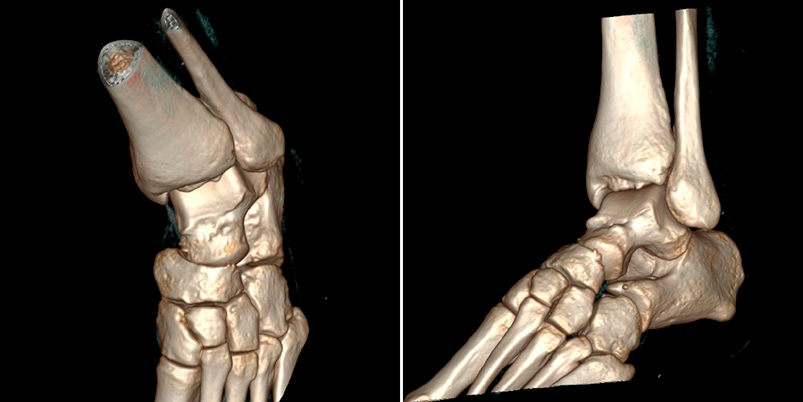

In computed tomography (CT), associated fractures in other bones of the foot, osteochondral lesions and intra-articular free bodies were ruled out (Figure 3).

Figure 3 3D CT reconstruction after close reduction with absence of associated fractures.